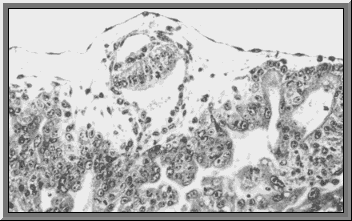

The hypoblast

The trophoblast gives rise to the hypoblast. The hypoblast will make up the inner covering of the blastocoel.

If the blastocoel is completely lined by hypoblast and trophoblast it is called the primary yolk sac.